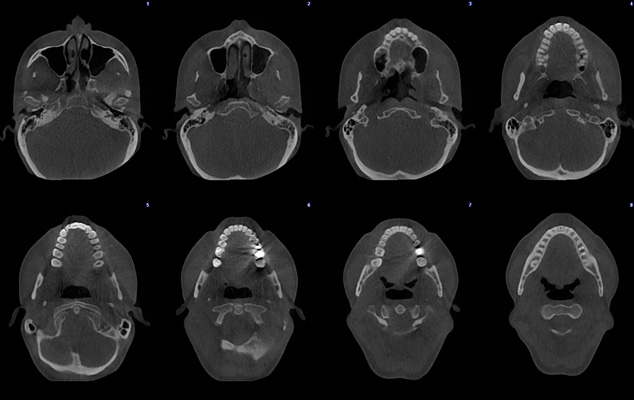

Obraz Ultra niska dawka - Cała czaszka

Planmeca ProMax 3D Mid - FOV Ø 200 x 170 mm. - Rozmiar Woksela 300 µm / 600 µm - Efektywna dawka dla pacjenta 14.7 µSv